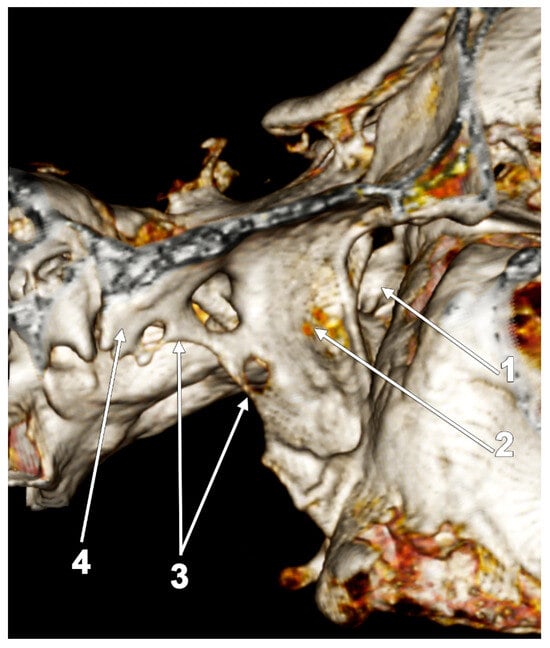

5.2. The Pterygospinous and Pterygoalar Bars

6. Aberrant Insertion Sites and Accessory Bundles of the Lateral Pterygoid Muscle